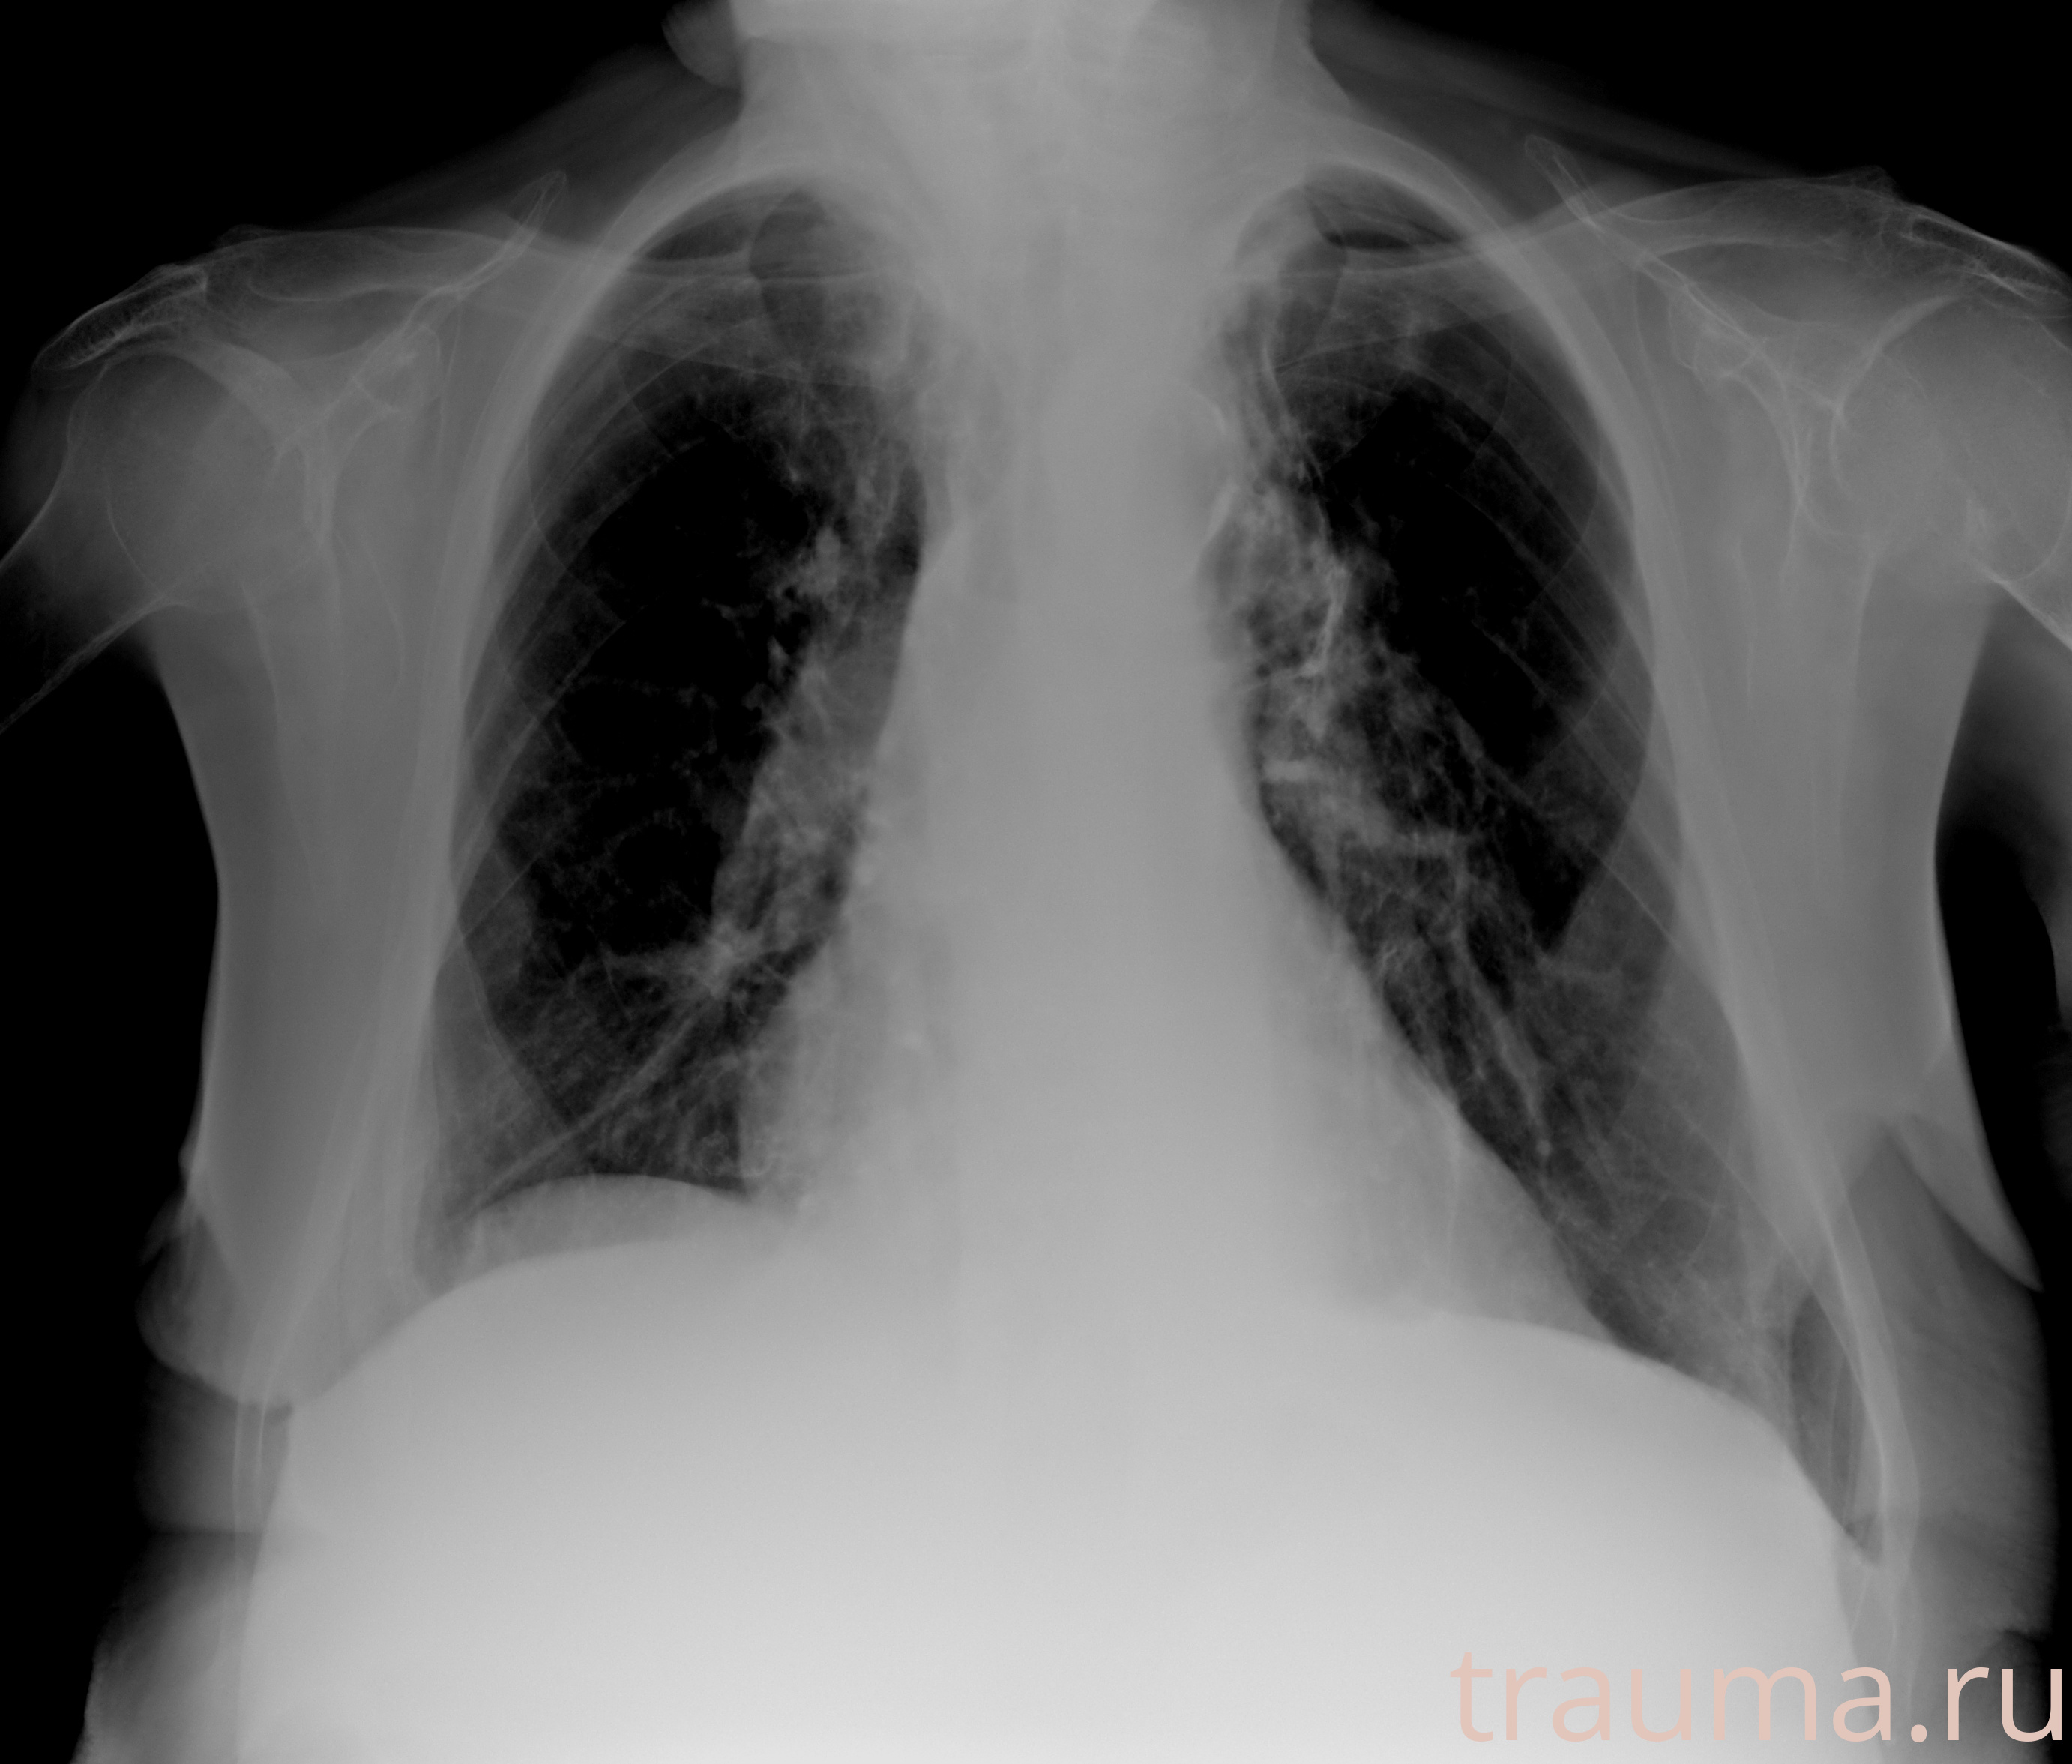

Рентгенограммы

Рентген на дому: по вашему адресу приезжает врач-рентгенолог, травматолог-ортопед с мобильным рентгеновским аппаратом, проводит диагностику травмы или заболевания, делает необходимые рентгенограммы, дает рекомендации по дальнейшему лечению. Получить качественные снимки в домашних условиях возможно благодаря уникальной методике, разработанной МосРентген Центром для института  Склифосовского

при переломе шейки бедра и пневмонии от компании МосРентген Центр - партнера Института имени Склифосовского